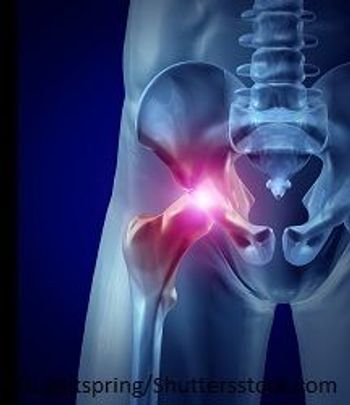

A study of patients undergoing total hip arthroplasty found that patients with psoriatic arthritis face no greater risk of poor outcomes than patients who get hip replacements because of osteoarthritis.

Study shows that patients with psoriatic arthritis and cutaneous psoriasis could be good candidates for total hip replacement.